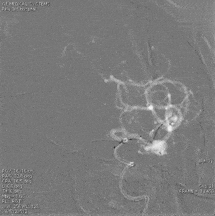

术后影像

复查标准正侧位造影, ICA、MCA、ACA主干及远端分支良好,动脉瘤栓塞满意。

术后工作位+侧位造影

术后正侧位透视

术后三维重建,支架贴壁良好,动脉瘤完全栓塞。